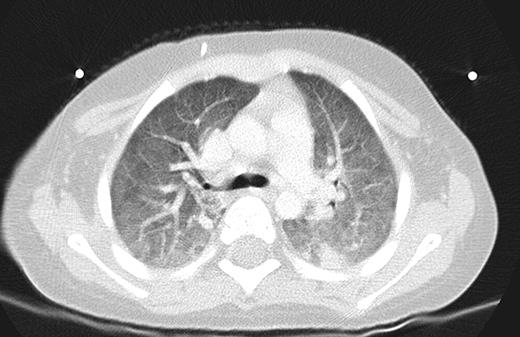

Our Patient, 8 weeks into chemotherapy for newly diagnosed ALL, presented with high grade fevers and poor activity. Patient was admitted 3 weeks prior for Bacillus cereus bacteremia. Additionally the patient had been on broad spectrum antibiotics on 2 occasions for febrile neutropenia episodes within the past 2 weeks. Patient had minimal respiratory symptoms at this presentation and recovered from pancytopenia at the time of this presentation. CT scans and chest x-ray (Figures 1 and 2) showed diffuse marked ground glass opacities with dependent consolidation in the lungs. On day 3 of admission, bronchoalveolar lavage (BAL) was preformed and empiric trimethoprim-sulfamethoxazole was initiated in addition to broad spectrum antibacterial, antifungal and antiviral medications.

Within 24 hours, patient rapidly deteriorated with significant respiratory distress and hypoxemia requiring intubation. Clinical and radiologic findings were suggestive of ARDS. Patient required significant ventilatory support, fluid restriction, diuretics, and steroids. PCR testing of BAL fluid was reported as positive for Pneumocystis jirovecii. By hospital day 6 the patient was still requiring a fair amount of respiratory support. Corticosteroids had been added but concern amongst some members of the team surrounded possible lack of efficacy of trimethoprim-sulfamethoxazole. Review of published case reports suggested that addition of caspofungin provided salvage therapy in cases where trimethoprim-sulfamethoxazole was believed to be suboptimal. Caspofungin was added to this patient's treatment. However, liver trans-aminases experienced a 2–3 fold increase within 72 hours after initiating caspofungin. Caspofungin was withdrawn but the patient's condition gradually improved and was extubated 7 days later. Also of note, there have been wide spread regional and national shortages of intravenous trimethoprim-sulfamethoxazole preparations. We were forced to convert to oral therapy several days after extubation. The patient continued to improve and had no signs of complications or increased morbidity from this conversion; however, this was a continued concern during his treatment.